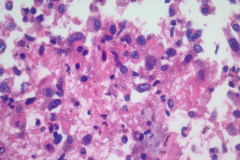

Specimen Type: FNA of RUL nodule. ThinPrep® Non-Gyn and conventional smears with Diff Quik stain, H&E stain (traditional cell block), Papanicolaou stain and AE1/AE3 (traditional cell block).

Cytology: Cytologically epithelioid sarcoma presents as numerous dispersed round, polygonal or spindle-shaped cells. Nuclei are large, vesicular, and eccentrically placed with small nucleoli. The nuclei can be single or multiple and pleomorphism may be present. The predominant arrangement is single cells, but they can also be arranged in sheets and loose cohesive clusters with fibrillary matrix. The cytoplasm is dense, may have small vacuoles with distinct cell borders. A background of necrosis is not uncommon.1-3